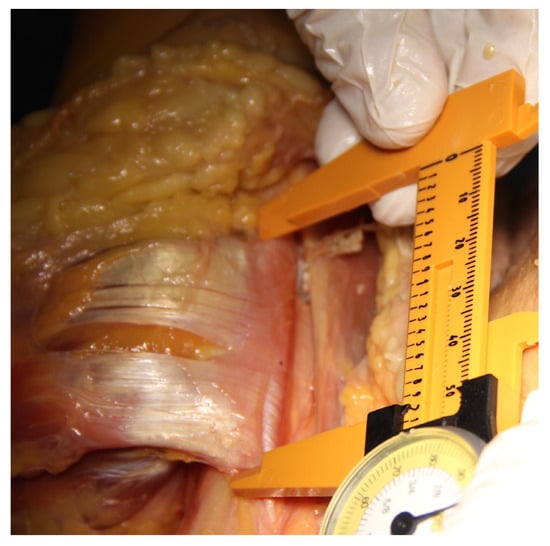

Dissection was performed following each tenodesis. The pectoralis major muscle was divided and its distal insertion everted so that the PMT could be evaluated from its deep surface (Figure 1). Manual calipers were used to measure the width of the PMT from proximal to distal at its point of insertion (PMT) (Figure 2), followed by the distance from the center of the reamed tenodesis tunnel in the anterior humeral cortex to the proximal border of the pectoralis major tendon (tunnel to PMT). The deltoid was then divided from the border of the acromion and dissection continued distally by developing the plane between the deltoid and the humerus until the axillary nerve and the cortical button were identified (Figure 1). Manual calipers were used to measure the distance from the center of the bicortical button on the posterior surface of the humerus to the axillary nerve (Button to AN). All the measurements were recorded for each specimen, including the diameter of the LHBT as measured with the tendon sizer. The 10 cadavers became available at different times, so the first 6 were studied by one primary researcher, and the last 4 were studied by another, all under the supervision and direct participation of the senior author.

Figure 2.

Anterior view of the ventral parts of a right shoulder. The pectoralis major muscle has been divided and the tendon is reflected laterally. The broad insertion of the pectoralis major tendon is seen here immediately lateral to the bicipital groove where it was measured with a manual caliper.